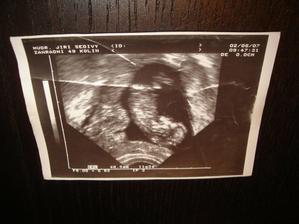

Naše zlatíčko Agátka - na svět přišla císařským řezem 5.2.2008